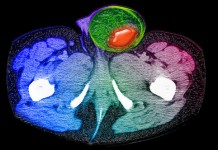

Паховая грыжа

Что такое паховая грыжа, почему она возникает, ее диагностика и лечение. Что такое паховая грыжа? Паховая грыжа возникает, если органы брюшной полости продавливается через уязвимые зоны...